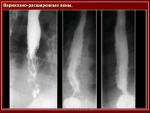

Варикозное расширение вен пищевода и желудка

Варикозное расширение вен пищевода и желудка является частым источником кровотечений из пищеварительного тракта у больных с синдромом портальной гипертензии. Варикозно расширенные вены в пищеводе больных цирро­зом печени рентгенологически выявляются в 14 - 80%, при этом может наблюдаться не только одновременное расширение вен пи­щевода и желудка, но также изолированное расширение вен же­лудка.

Рентгенологический ме­тод исследования является основным в диагностике варикозного расширения вен пище­вода и желудка. При исследовании используют жидкую и густую барие­вую взвесь. Наиболее оптимальным кон­трастным веществом считается густая взбитая танинобариевая смесь, применяемая для изучения рельефа слизи­стой оболочки. Изучение функционального состояния органов в конце исследования производят с жидкой бариевой взвесью. Исследование проводят в вертикальном и горизонтальном по­ложении больного, наиболее информативно исследование в горизонтальном поло­жении на животе с поворотом на правый бок.

Клинико-рентгенологическая классификация варикознорасширенных вен пищево­да и желудка включает четыре степени в зависимости от выраженности и распро­страненности патологического процесса: 1 степень - незначитель­ные, начальные расширения вен, 2 степень - умеренно выраженные, 3 степень - отчетливо выраженные, 4 степень - резко выраженные расширения вен.

К наиболее ранним функциональным симптомам варикозного расши­рения вен пищевода относится тотальная или чаще сегментарная гипотония пищевода, его расширение и медленный пассаж ба­риевой взвеси, ослабление перистальтики и дискоординация функ­ции пищевода. При этом, атония пищевода считается предстадией варикозного расширения вен. Наи­более ранним рентгенморфологическим симптомом является образование утолщенных складок слизистой оболочки с волнистыми очертаниями. В случаях выраженного варикозного расширения вен пищевода на фоне несколько измененного рельефа слизистой оболоч­ки, имеющего ячеистый или кружевной вид, выявляются множест­венные дефекты наполнения округлой или овальной формы. Варикоз­ные узлы часто располагаются цепочками по ходу вен в виде об­разований, напоминающих полипы, или в виде коротких извилистых прозрачных полосок разной величины. Практически постоянным симптомом являются краевые дефекты, обусловливающие неровность контуров пище­вода, по типу «изъеденной молью» или «нитки жемчуга». Бариевая взвесь задерживается между дефекта­ми наполнения в виде отдельных помарок. У ряда больных выявляется выраженная картина недостаточности кардии и рефлюкс-эзофагита.

Типичная локализация варикозного расширения вен пищевода - нижняя треть пищевода. Протяженность процесса является косвенным пока­зателем тяжести процесса, в определенной мере ее можно исполь­зовать и для определения прогноза, при этом имеет значение также анатомическое строение венозной сети.

При варикозном расширении вен отсутствует явное сужение просвета пищевода, эластичность и сократительная способность стенок не нарушаются. Размеры дефектов наполнения меняются при приеме густой бариевой взвеси, сдавливающей варикозные узлы, а также под влиянием функ­циональных проб, покашливания и перемены положения тела. При сокращении пищевода узлы могут исчезать, а при расслаблении - появляться вновь. Варикозное расширение вен может появляться и исчезать в зависимости от выраженности цирроза.